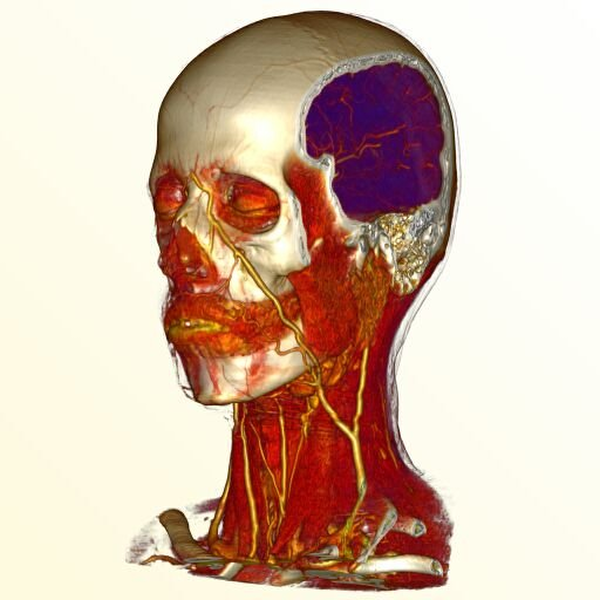

Sören Grimm, Stefan Bruckner , Armin Kanitsar, Eduard Gröller , Armin Kanitsar, Eduard Gröller Memory Efficient Acceleration Structures and Techniques for CPU-based Volume Raycasting of Large Data In Proceedings IEEE/SIGGRAPH Symposium on Volume Visualization and Graphics, pages 1-8. October 2004. [  Paper] Paper] |